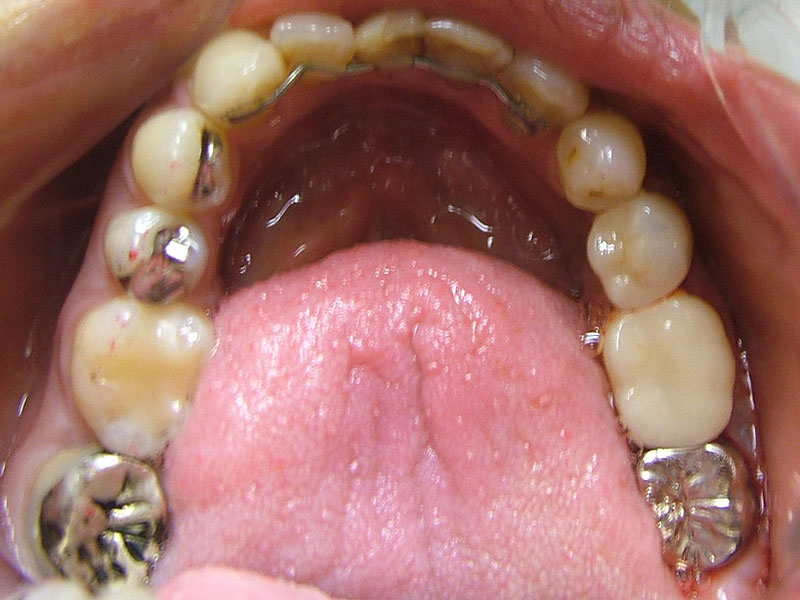

術前

- 初診:2006年。2010年―矯正治療を含めた一口腔単位の治療開始、治療当時、30代女性、喫煙者

- 主訴:虫歯治療、歯周病治療、できれば歯並びも治したい。

- 矯正診断:3級骨格性の反対咬合

- 治療方針:以前に治療した歯の再治療(虫歯治療、歯内療法、歯周処置)、右下前歯1本抜歯、矯正用インプラントを用いたワイヤー矯正、修復処置(被せ物)、保定(上ワイヤー、下マウスピース)、歯茎のピーリング(漂白)、4か月メンテナンス